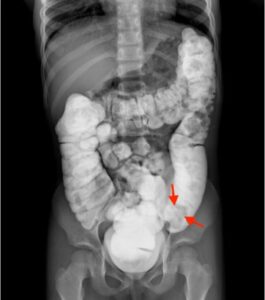

Colocolic Intussusception. Contrast Enema, Annotated. JETem 2024

Colocolic Intussusception. Contrast Enema Annotated. JETem 2024